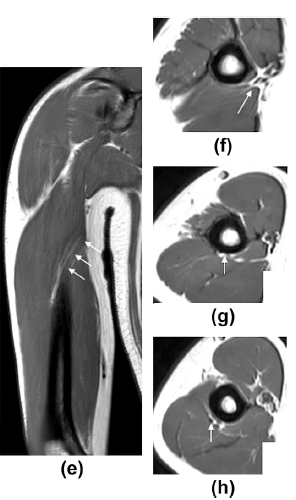

아래쪽의 단단한 '상완골'과

뒤쪽의 '상완삼두근 외측두'

(Lateral head of Triceps) 라는

가해자 사이에

요골신경이라는

피해자가 끼어있는 구조죠.

팔을 많이 써서 삼두근과 주변 근막이

딱딱하게 긴장되고 유착되면서

이 공간이 좁아지고

요골 신경이 눌리게 되는 것이죠.